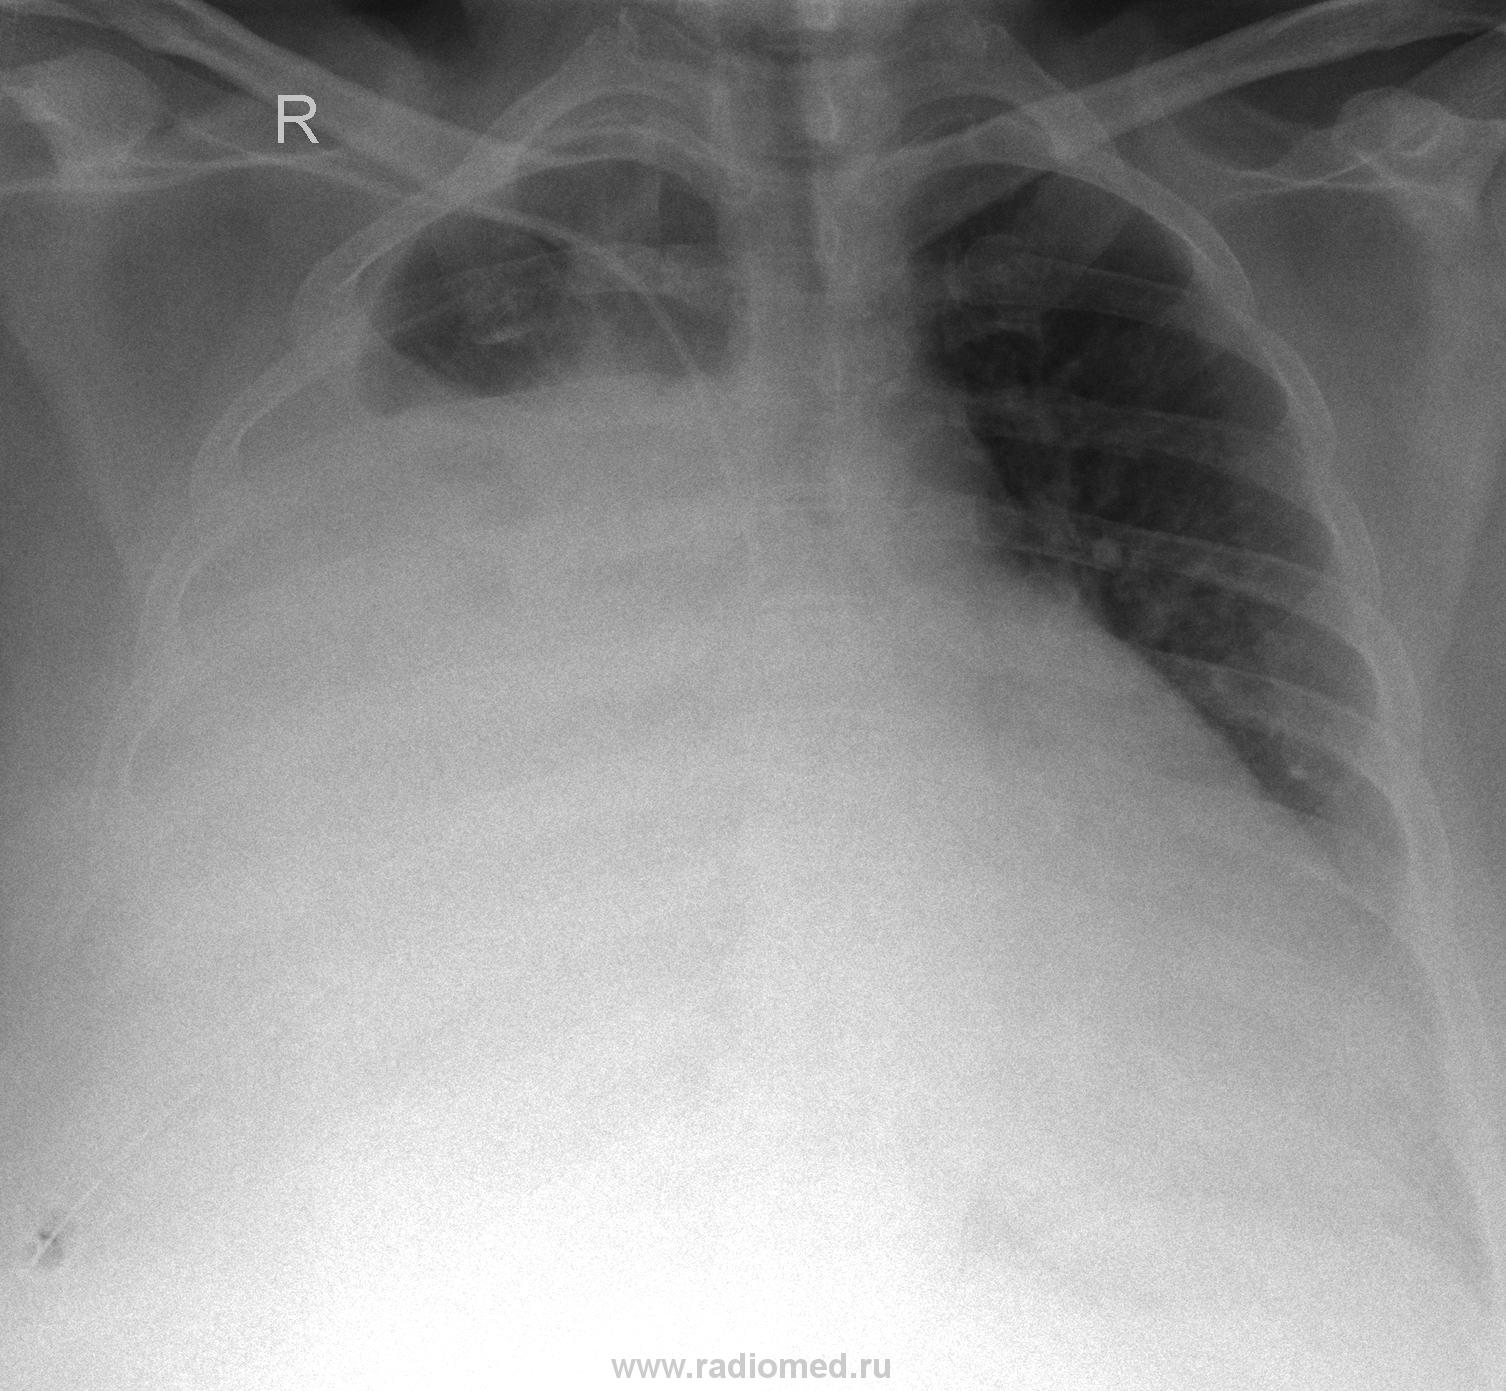

Всё же данная картина была описана как наличие гемопневмоторакса с компрессионным ателектазом легкого. Плотность жидкости варьирует в пределах 30-55HU. Сделали контроль после дренирования:

Валентин Львович это ещё ни всё, сегодня утром сделали контроль, динамика на лицо:

А поповоду "классики" всё я как изночально предпологал так оно получилось по результатам МСКТ, а заключение сделал такое "ЗАКЛЮЧЕНИЕ:Оссумкованный паракостальный плеврит справа. Компрессионный ателектаз правого легкого. Связи раннее выполненной плевральной пункцией не искл. гемопневмоторакс справа."